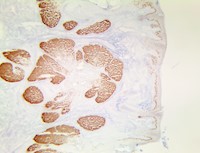

TintoFast PRAME antibody overexpression in triple negative breast cancer has also been found to promote cancer cell motility through induction of the epithelial-to-mesenchymal transition. PRAME mRNA expression is well documented in Cutaneous and Ocular Melanomas. One study concluded that diffuse nuclear immunoreactivity for PRAME was found in 87% of metastatic and 83.2% of primary Melanomas. Among Melanoma subtypes, PRAME was diffusely expressed in 94.4% of acral Melanomas, 92.5% of superficial spreading Melanomas, 90% of Nodular Melanomas, 88.6% of Lentigo Maligna Melanomas, and 35% of Desmoplastic Melanomas. When in situ and NonDesmoplastic Invasive Melanoma components were present, PRAME expression was seen in both. Most Melanocytic nevi (86.4%), were completely negative for PRAME.

Immunoreactivity for TintoFast PRAME was seen, albeit usually only in a minor subpopulation of lesional Melanocytes, in 13.6% of Cutaneous Nevi, including Dysplastic Nevi, Common Acquired Nevi, Traumatized/recurrent Nevi, and Spitz Nevi. Rare isolated junctional Melanocytes with immunoreactivity for PRAME were also seen in Solar Lentigines and benign nonlesional skin. This study suggests that immunohistochemical analysis for PRAME expression may be useful for diagnostic purposes to support a suspected diagnosis of Melanoma. It may also be valuable for margin assessment of a known PRAME-positive Melanoma, but its expression in Nevi, Solar Lentigines, and Benign nonlesional Skin can represent a challenge.